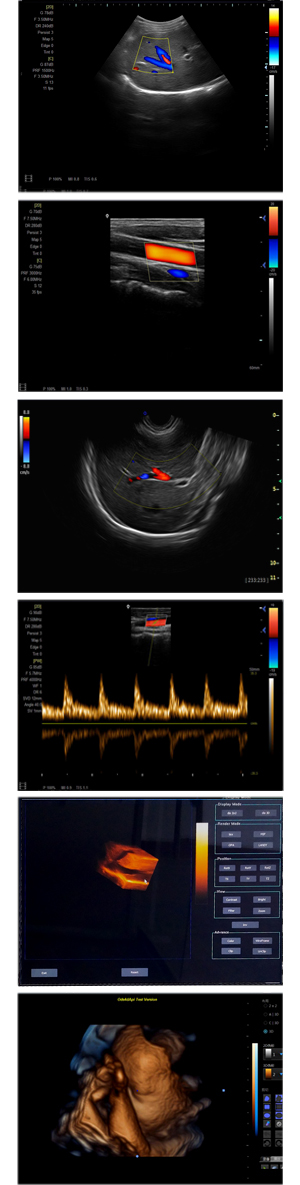

XF-7500型,秉承先鋒彩超技術之精華,擁有高雅大氣的獨特外型,為最新一代應用型數字彩色多普勒診斷系統,魅力與實力相融合。可廣泛適用于腹部、婦產科、心臟、小器官、乳腺、肌骨及外周血管等諸多方面的診查,讓您在臨床超聲診斷應用領域得心應手,綻放異彩!

● 3D/ 4D成像技術/選配

● 應用于腹部、腎臟、泌尿系統、產科、婦科、盆腔、大動脈、肌肉組織、小器官、乳腺、心臟等

● 能量多普勒成像(PDI)

● 彩色血流量圖(CDE)

● 脈沖頻譜多普勒成像(PW)